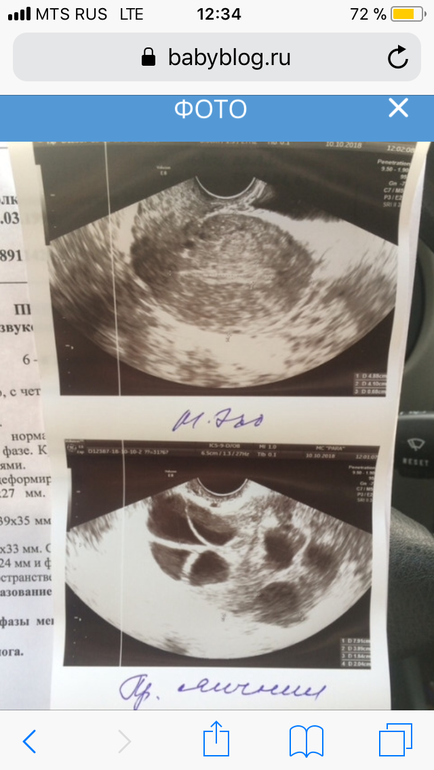

ЭКО по квоте и полису ОМСВсем здравствуйте! Получала первую квоту в августе, протокол был в сентябре. Сейчас надо получить вторую квоту, чтобы вступить в протокол в конце ноября - начале декабря. Дадут ли квоту с таким УЗИ? Яичники большие после протокола((( но я их не ощущаю болей никаких нет.

Да вас прям сейчас хоть повторно пунктируй.

В протокол нельзя в ближайшее время это точно

Елена

Про тоже подумала... столько больших фолликов...

У меня в начале след. цикла после стимуляции яичники были совсем немного увеличивались, осталось 1 ЖТ уходящее, а здесь как второй этап стимуляции...

Ромашка

Да просто видимо врач мелкие не пропунктировал. Так делать, конечно, нельзя.